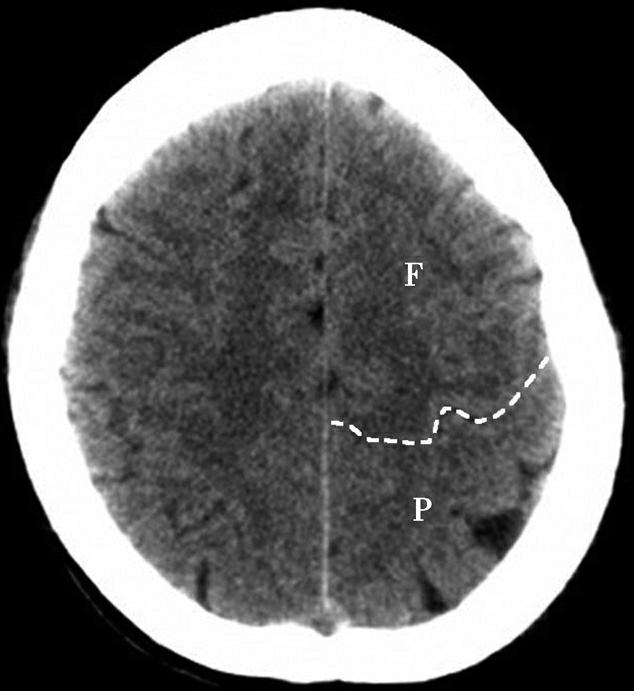

Alberta卒中项目早期CT评分(Alberta stroke program early CT score,ASPECTS)是一种评价急性缺血性卒中患者大脑中动脉供血区早期缺血性改变的简单、可靠、系统化的方法,是常用的脑卒中评定量表之一,可对缺血性病变快速进行半定量评价,有助于判定溶栓效果和远期预后。该评分主要基于CT平扫,具体分区如下(图1-2-76)所示,即选取大脑中动脉供血区2个层面。分区后共10个区域,每个区域记1分。评分时任何区域只要有低密度灶,则扣除该区域得分。正常脑ASPECTS评分为满分(10分),若MCA供血区广泛梗死累及全部区域时,则ASPECTS评分为0分。

图1-2-76 ASPECTS评分脑组织分区

A.在基底节层面(即丘脑和纹状体平面),分为各级分支M 1 、M 2 、M 3 、岛叶(缩写I)、豆状核(缩写L)、尾状核(缩写C)和内囊(缩写IC)后肢等7个区域;B.在基底节以上层面(基底节层面上2cm),包括M 4 、M 5 和M 6 。